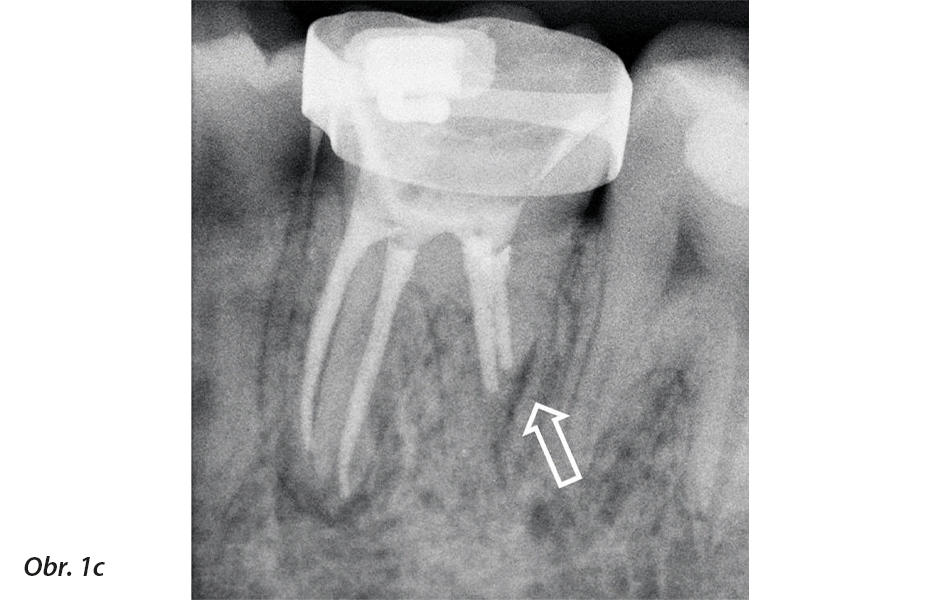

V meziálních kanálcích byla vytvořena manuálně glide path pomocí K-file ISO 15 a ISO 20 (Dentsply/Maillefer), pak následovala preparace s využitím techniky plné sekvence nástrojů dvou systémů (VDW). Velikost distálních kanálků vyžadovala manuální preparaci až do velikosti K-file ISO 60 (Dentsply/Maillefer), a to podle principů crown-down techniky. Průchodnost kořenových kanálků byla udržována použitím K-file ISO 20 (Dentsply/Maillefer) až k hlavnímu foramen. Kanálky byly vyplachovány při každé změně nástroje s 2,5 ml 2,5% chlornanu sodného a konečný výplach byl proveden s 2,5 ml 17% EDTA (Fórmula & Ação) po dobu tří minut, aby se odstranila smear layer. Kořenové kanálky byly poté vysušeny absorpčními papírovými čepy (Dentsply/Maillefer) a zaplněny gutaperčovými čepy (Dentsply/Maillefer) a sealerem AH 26 (Dentsply/Maillefer) (obr. 1b) za použití metody laterální kondenzace. Šest měsíců po léčbě se pacient vrátil k následné kontrole a neuváděl žádnou bolest ani žádnou relevantní symptomatologii. Radiografické vyšetření ukázalo jasné důkazy o hojení tkáně a omezení resorpčního procesu (obr. 1c).

Rentgen po 6 měsících od ošetření s jasnými známkami hojení tkání a omezením resorpčního procesu (šipka).